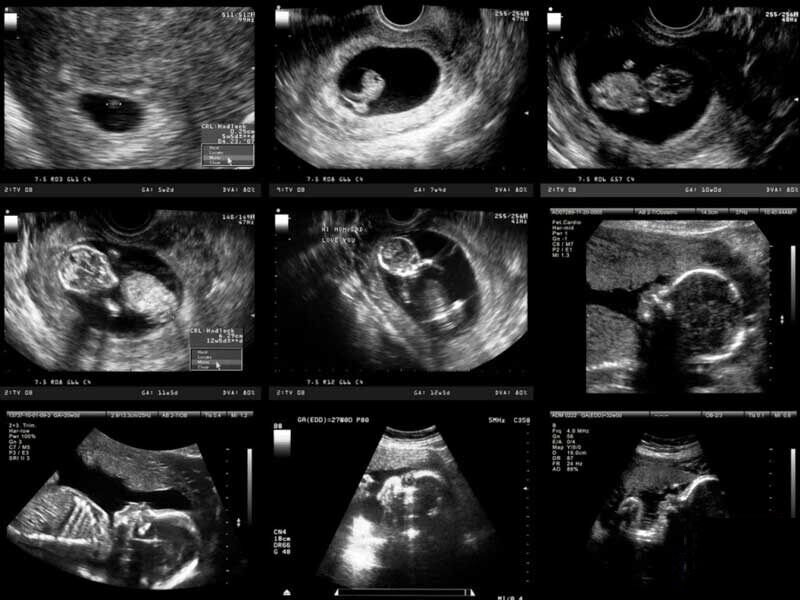

دکتر فیروزه احمدی متخصص سونوگرافی و رادیولوژی در ارتباط با سونوگرافیهای مهم و روتین که در بارداری استفاده میشود توضیح می دهد: «اولین سونوگرافی که معمولا درخواست میشود در هفته ۶ تا ۷ بارداری است؛ برای مشخص کردن محل ساک بارداری، تعداد ساک و جنینها و همچنین دیدن ضربان قلب. سونوگرافیهای روتین بعدی با این سونوگرافی اول از نظر رشد جنین مقایسه میشود.»

این متخصص سونوگرافی ادامه می دهد : «سونوگرافی بعدی که اصطلاحا به آن غربالگری اول گفته میشود، معمولا بین هفته ۱۱ تا ۱۳ انجام میشود. طی این غربالگری ضخامت پشت گردن جنین را اندازه گیری میکنند و ناهنجاریهای اساسی و مهم که ممکن است در این سن خود را نشان بدهند، بررسی میشود.»

عضو هیئت علمی پژوهشگاه رویان ادامه می دهد : «به سونوگرافی بعدی که انجام میشود غربالگری دوم گفته میشود که اصولا بین هفته ۱۸ تا ۲۲ است. این سونوگرافی غربالگری در کشور ما قبل از هفته ۲۰ انجام می شود که بازدر آن رشد جنین را بررسی و مقایسه میکنند. در این سن ناهنجاریهایی که ممکن است جنین در ظاهر داشته باشد و همچنین علائمی که ممکن است نشان دهنده بعضی از سندرومهای مادرزادی باشد قابل بررسی است. ولی مهمترین علل انجام این سونوگرافی عبارتند از: بررسی رشد جنین، میزان مایعی که دور جنین است، بررسی ضربان قلب جنین و ناهنجاریهایی که ممکن است در ظاهر جنین مشخص باشد. سونوگرافی بعدی اگر لازم باشد معمولا بین هفته ۲۸ تا ۳۲ است که مجددا بررسی وزنگیری، میزان مایع و رشد جنین است. موقعیت جنین و جفت برای این که پزشک در ارتباط با زمان زایمان تصمیم بگیرد مشخص میشود و اگر لازم باشد داروهای لازم و متناسب با رشد جنین به مادر داده میشود.»